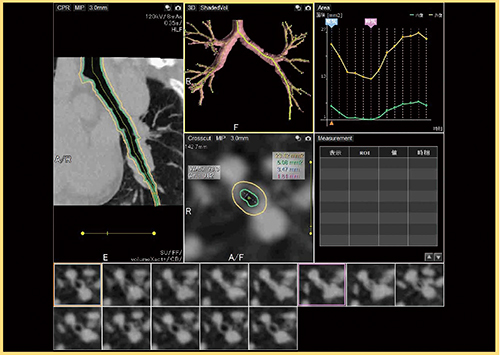

薬事承認されたばかりの「4D気管支トラッキング」(東芝メディカルシステムズ)は,四次元の気管支データを定量的に解析し,COPDによる気管支形態評価や気管軟化症診断を行うためのソフトウエアである。データから気管支を自動抽出し,観察したい任意の気管支を選択することで断面を自動的に追跡し解析を行う。解析結果は4D表示されるとともに,内腔径や面積を算出し,位相ごとの変化がグラフで表示される。

症例1は現喫煙者の患者で,肺実質内に気腫が目立ち,Flow Volume Curveからはかなり気流の制限があることがわかる(図3)。動態撮影をよく見ると,左右の横隔膜の動きにズレがあることからも気流の制限が疑われる。4D気管支トラッキングで解析すると,左下葉の気管支断面が,呼気時に非常に強く狭窄することが観察された(図4)。

図4 症例1の4D気管支トラッキング解析結果